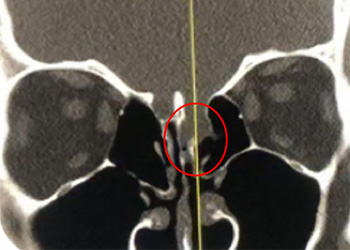

Brain:

Pituitary Tumor with Cushing’s Disease

Author: Michael Brisman M.D., F.A.C.S., Read More!